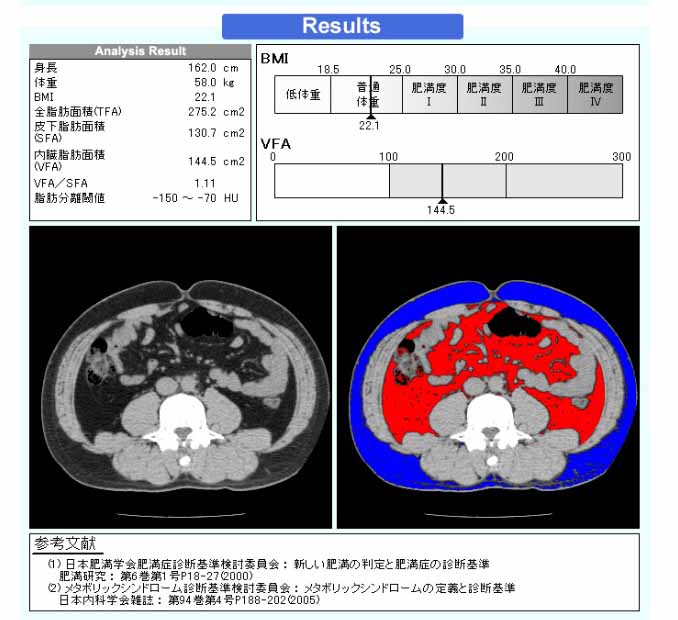

- 内臓脂肪